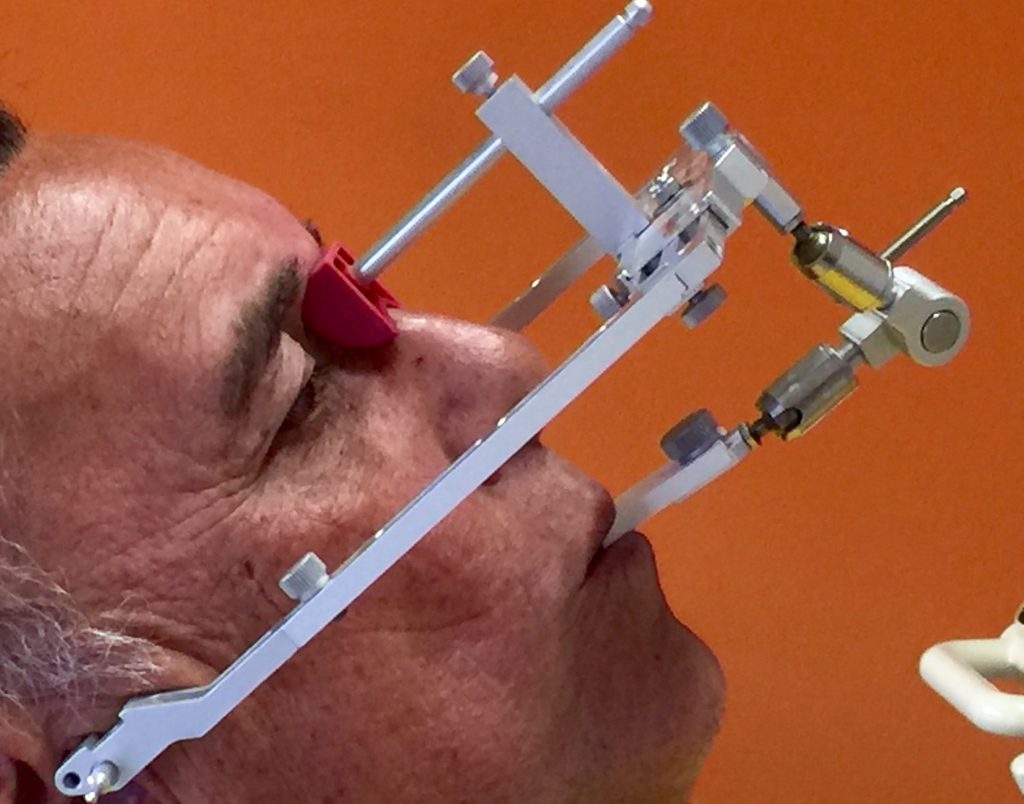

Autores: PRÓLOGO Asimismo, desde el punto de vista pedagógico, el profesional nobel en la materia tiene a su alcance la posibilidad de corregir cualquier posición implantaría en el ordenador, planear los provisionales y plasmarlos en la bio réplica antes de tocar al paciente a operar. Todos estos razonamientos nos llevan a presentar un caso de condiciones muy favorables para poner en práctica estos métodos como primer acercamiento a una Odontología Digital de alta calidad, con medios informáticos, que ya están presentes en la profesión de hoy en día, y será la protagonista única del futuro. Por otro lado, después de numerosos estudios que nos llevan a plantear el “gap” entre implante y pilar(abuttment), como principal responsable de la periimplantitis dado que la microbiota presente en el mismo es imposible de limpiar y en su presencia la cortical ósea reacciona reabsorbiéndose, nos ha llevado a utilizar implantes monobloc ya que los ejes implantarios y protéticos coincidían, y nos permitían su uso. Además, el circonio, ha mostrado a la luz de estudios muy recientes, una preservación y adhesión de los tejidos blandos superiores al titanio, tanto en su tratamiento de superficie de la rosca como a nivel gingival. DESARROLLO Paciente varón de 68 años, con antecedentes de radio/quimioterapia cinco años antes, con Rehabilitación Oral de los cuatro cuadrantes, con una Oclusión Mutuamente Compartida conservada, (REF.8) la que fracasa en el cuadrante 4, 19 años después. El mismo presentaba un puente de porcelana sobre circonio con pilares en 44 y 47, reemplazando el edentulismo de 45 y 46. Se produce la fractura del PM del 44, y ante una endodoncia antigua y corta, se decide implantar las zonas edéntulas, conservando temporariamente los pilares, hasta producida la oseointegración, para entonces también exodonciar el 44. DIAGNÓSTICO Tomamos impresiones del maxilar antagonista, Arco Facial Estático y realizamos montaje del mismo mediante la sistemática ARTEX. Producimos la relajación del músculo Pterigoideo Externo, para obtener la ORC (Oclusión en Relación Céntrica) mediante el método de Laminillas de Long, basado en el concepto de INERVACIÓN RECÍPROCA. Esto nos permitirá montar el maxilar inferior, tanto en su forma de: La primera para practicar la cirugía guiada y comprobar su eficacia, y el modelo de yeso para ser escaneado y confeccionar la GUÍA QUIRÚRGICA. La Biorréplica la obtenemos transformando los archivos DICOM que nos da el CBCT en archivos STL, y a partir de ellos, mediante una tecnología de PROTOTIPADO RÁPIDO, la obtención de un objeto físico en 3D a través de la aglutinación selectiva de una sucesión de capas de polvo. Procedemos a montar la biorrèplica y el modelo de yeso del caso. Podemos verificar la exactitud de las medidas del hueso residual en la bio réplica y compararlas con el scanner. Arrojando un resultado de 8,5 mm de cortical externa a cortical externa. Pudiendo también medir la distancia hasta el dentario. y comparar gracias a la ventana lateral de la biorréplica Dándonos 22mm de distancia. Con lo cual deducimos que implantes de 4,1mm por 12 mm serán perfectamente rodeados de hueso. Medimos también la distancia desde oclusal del antagonista, hasta el hueso desnudo. Lo mismo que, mediante la utilización de la guía radiológica, con un material radiolúcido colocado en gingival de la misma, podemos medir la altura de la encía. Con lo cual podemos calcular la altura del pilar. Es entonces cuando con el programa COC Diagnostix se realiza la programación final: Obteniendo no solo la ubicación, largo, ancho y ángulo de los implantes sino también los provisionales mediante CAD CAM. Ya entonces podemos hacer la práctica quirúrgica en la bio réplica, mediante la guía quirúrgica, instalando los implantes de prueba que no serán los de circonio, ya que la casa no cuenta con ellos, pero si otros de las mismas dimensiones. TRATAMIENTO Entramos ya en la cirugía propiamente dicha. Antisepsia de la zona a operar y zonas anexas. Comprobación del perfecto ajuste e inmovilidad de la G.Q. en boca durante la cirugía. Marcado de la encía y perforación de la cortical. Visión a través de la Guía de la mínima intervención anterior. Comprobación sin Guía. Incisión mínima mesio distal, para apartar y conservar encía queratinizada. Secuencia de drills, perforando a profundidad requerida Observación del Mínimo Trauma Implantes Strauman de Zirconio Monoblock en blíster y montádo en contrángulo reductor. Instalación controlando torque con contrángulo reductor. Comprobación clínica. Comprobación Radiográfica y con Guía. Toma de impresiones, y armado de modelos con técnicas de pasividad protética. Montaje. Resultado de las provisionales ejecutadas por CAD CAM Al no estar conformes con el resultado decidimos desechar dichas provisorias y optar por repetirlas. Nuevas provisorias realizadas mediante encerado convencional. Estado de los tejidos blandos. Provisorias en boca. Oclusión de Estímulo Inmediato. Ref.10: Carga inmediata .Alberto y Diego Bechelli. Comprobación mediante CBCT post operatorio Componentes del equipo (En la próxima presentación, mostraremos las coronas definitivas de porcelana sobre circonio, y la desoclusión provocada por una OCLUSIÓN MUTUAMENTE COMPARTIDA, sobre estos implantes y otros seis mas) REFERENCIAS

FIG: 1-2-3-4

FIG: 5-6-7-8

FIG: 9-10-11-12